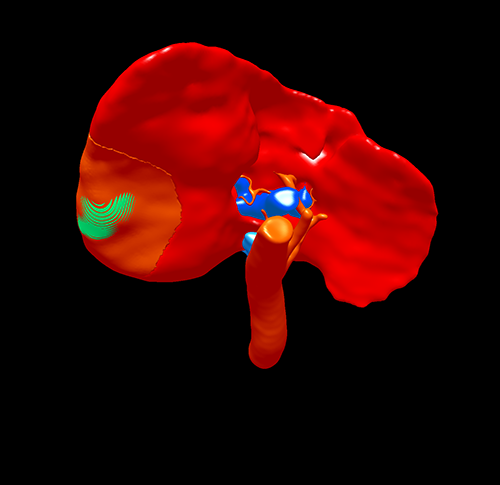

S67肝癌--腹腔镜S67切除